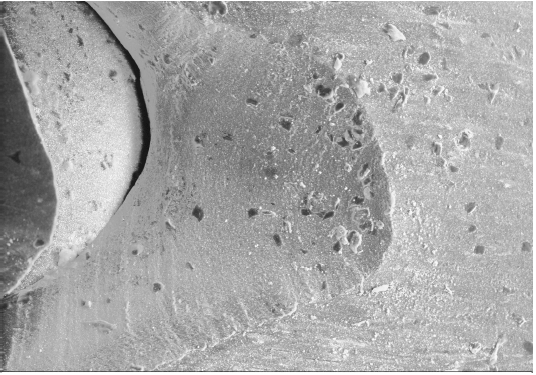

Bild 2

Auf Bild 2 ist mit 80-facher Vergrößerung zu sehen, wie die darunter liegende Fläche aussieht. Dabei fällt auf, insbesondere an den unteren Seitenflächen, dass eine wellenförmige Kante des Risses existiert, bei genauem Hinsehen lassen sich diese Wellen auch bogenförmig über die Rissfläche hinweg erkennen. Diese wellenförmigen Strukturen sind typisch für reißendes Silikon. Silikonkautschuk ist ein Material, das sehr kerbempfindlich ist, das z.B. als Schlauch verarbeitet primär eine geringe Reißneigung hat, die Reißneigung steigt aber erheblich, wenn es vorgekerbt ist. Auf Bild 2 am rechten Rand der Bruchfläche sind die wellenförmigen Rissstrukturen nicht eindeutig zu erkennen, es sind andererseits aber auch keine ganz eindeutigen Schnittspuren zu sehen. Auffällig ist weiterhin, dass sowohl die Katheteroberfläche als auch die Rissfläche mit zahlreichen kleinen organischen Auflagerungen belegt sind, die, ohne dies analysiert zu haben, als Fibrinauflagerungen zu interpretieren sind. Aus der Zusammenschau dieser Befunde ergibt sich folgende Erklärung mit an Sicherheit grenzender Wahrscheinlichkeit: